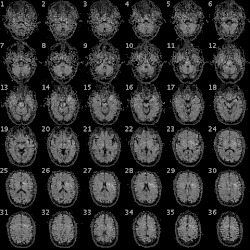

Composite images from an fMRI scan

Physicians use fMRI to assess how risky brain surgery or similar invasive treatment is for a patient and to learn how a normal, diseased or injured brain is functioning. They map the brain with fMRI to identify regions linked to critical functions such as speaking, moving, sensing, or planning. This is useful to plan for surgery and radiation therapy of the brain.